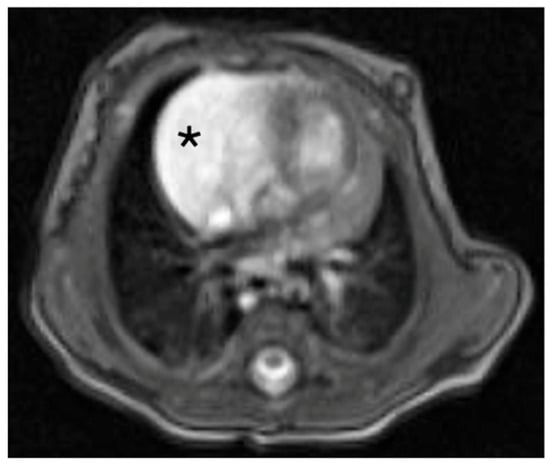

Intrapericardial Extralobar Pulmonary Sequestration: A Case Report and Systematic Review of a Unique Embryologic Variant

Background: Intrapericardial extralobar pulmonary sequestration (ELPS) is an exceptionally rare congenital malformation. The location may mimic neoplastic lesions and poses diagnostic and surgical challenges. We present a new case and a systematic review of the literature. Case Presentation: A 3-month-old male infant was referred for evaluation of a congenital intrathoracic mass suspected to be an extralobar sequestration. However, intrapericardial location was not recognized. MRI and CT demonstrated a circumscribed lesion with arterial supply from the right pulmonary artery. Thoracoscopic exploration was attempted but converted to sternotomy. The mass was excised en bloc. Histopathological analysis confirmed extralobar pulmonary sequestration with cystic components, consistent with a hybrid lesion. Postoperative recovery was uneventful. Methods: A systematic literature review was conducted according to PRISMA guidelines across PubMed, Scopus and Embase databases, including only histologically confirmed intrapericardial ELPS. Results: Ten cases were identified. Including the present case, eleven cases have been reported. Prenatal detection occurred in 54% of cases. Fetal demise occurred in two cases due to cardiac tamponade. Aberrant arterial supply originated from the pulmonary arteries in 54% of patients and venous drainage into the right atrium or superior vena cava in 45%. Surgery via sternotomy was performed in all cases with excellent outcomes. Conclusions: Intrapericardial ELPS is an exceptionally rare but surgically curable entity. Early recognition and complete resection are essential to prevent life-threatening complications. This systematic review highlights a consistent vascular pattern supporting its classification as a unique embryologic variant within the CPAM–sequestration spectrum. Full article

Figure 1